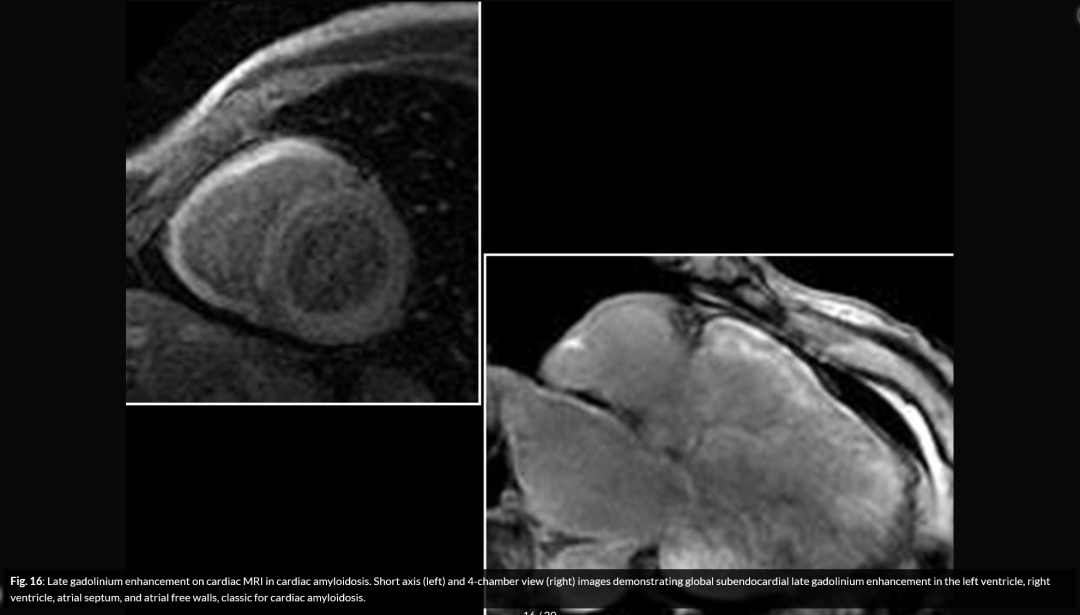

心脏MR:

淀粉样纤维心肌沉积增加心脏体积(ECV),全心心内膜下延迟性钆对比的增强(LGE),在检测LV增厚之前也可以识别T1信号异常ECV测量可能能够区分CA并且可用于监测进展;透壁增强模式与较差的预后相关,并且是死亡率的独立预测因子。心脏MR直观、可定量,但不能很好地鉴别CA亚型,目前还在研究阶段。